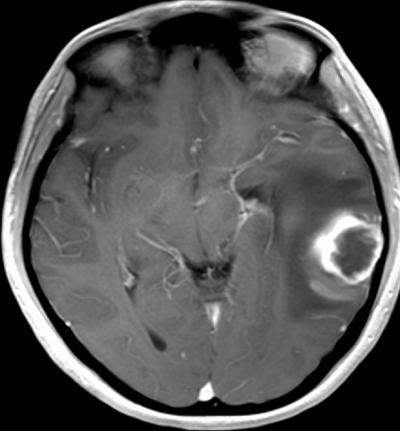

UCLA researchers have uncovered a new way to scan brain tumors and predict which ones will be shrunk by the drug Avastin -- before the patient ever starts treatment. By linking high water movement in tumors to positive drug response, the UCLA team predicted with 70 percent accuracy which patients' tumors were the least likely to grow six months after therapy.

The UCLA team studied 82 patients who had undergone surgery and radiation therapy to remove glioblastoma. Half of the patients received infusions of Avastin every two weeks. All underwent monthly brain scans by magnetic resonance imaging (MRI) to monitor change.

The researchers analyzed the MRI scans of the patients whose tumors returned. Explaining what the team saw requires an understanding of how the tumor creates an independent blood supply.

This process launches a chain of events that is detectable by MRI. Oxygen-starved cells produce more VEGF, which causes blood vessels to leak fluids into the tumor and surrounding tissue. This results in swelling, which boosts water's ability to move freely in the tumor and brain tissue. As cells disintegrate, they no longer pose a physical barrier to water movement.

By measuring the amount of water motion within the tumor, the researchers were able to predict with 70 percent accuracy which patients' tumors would progress within six months and which would not. They detected greater water movement in the tumors of those persons who later responded best to Avastin.